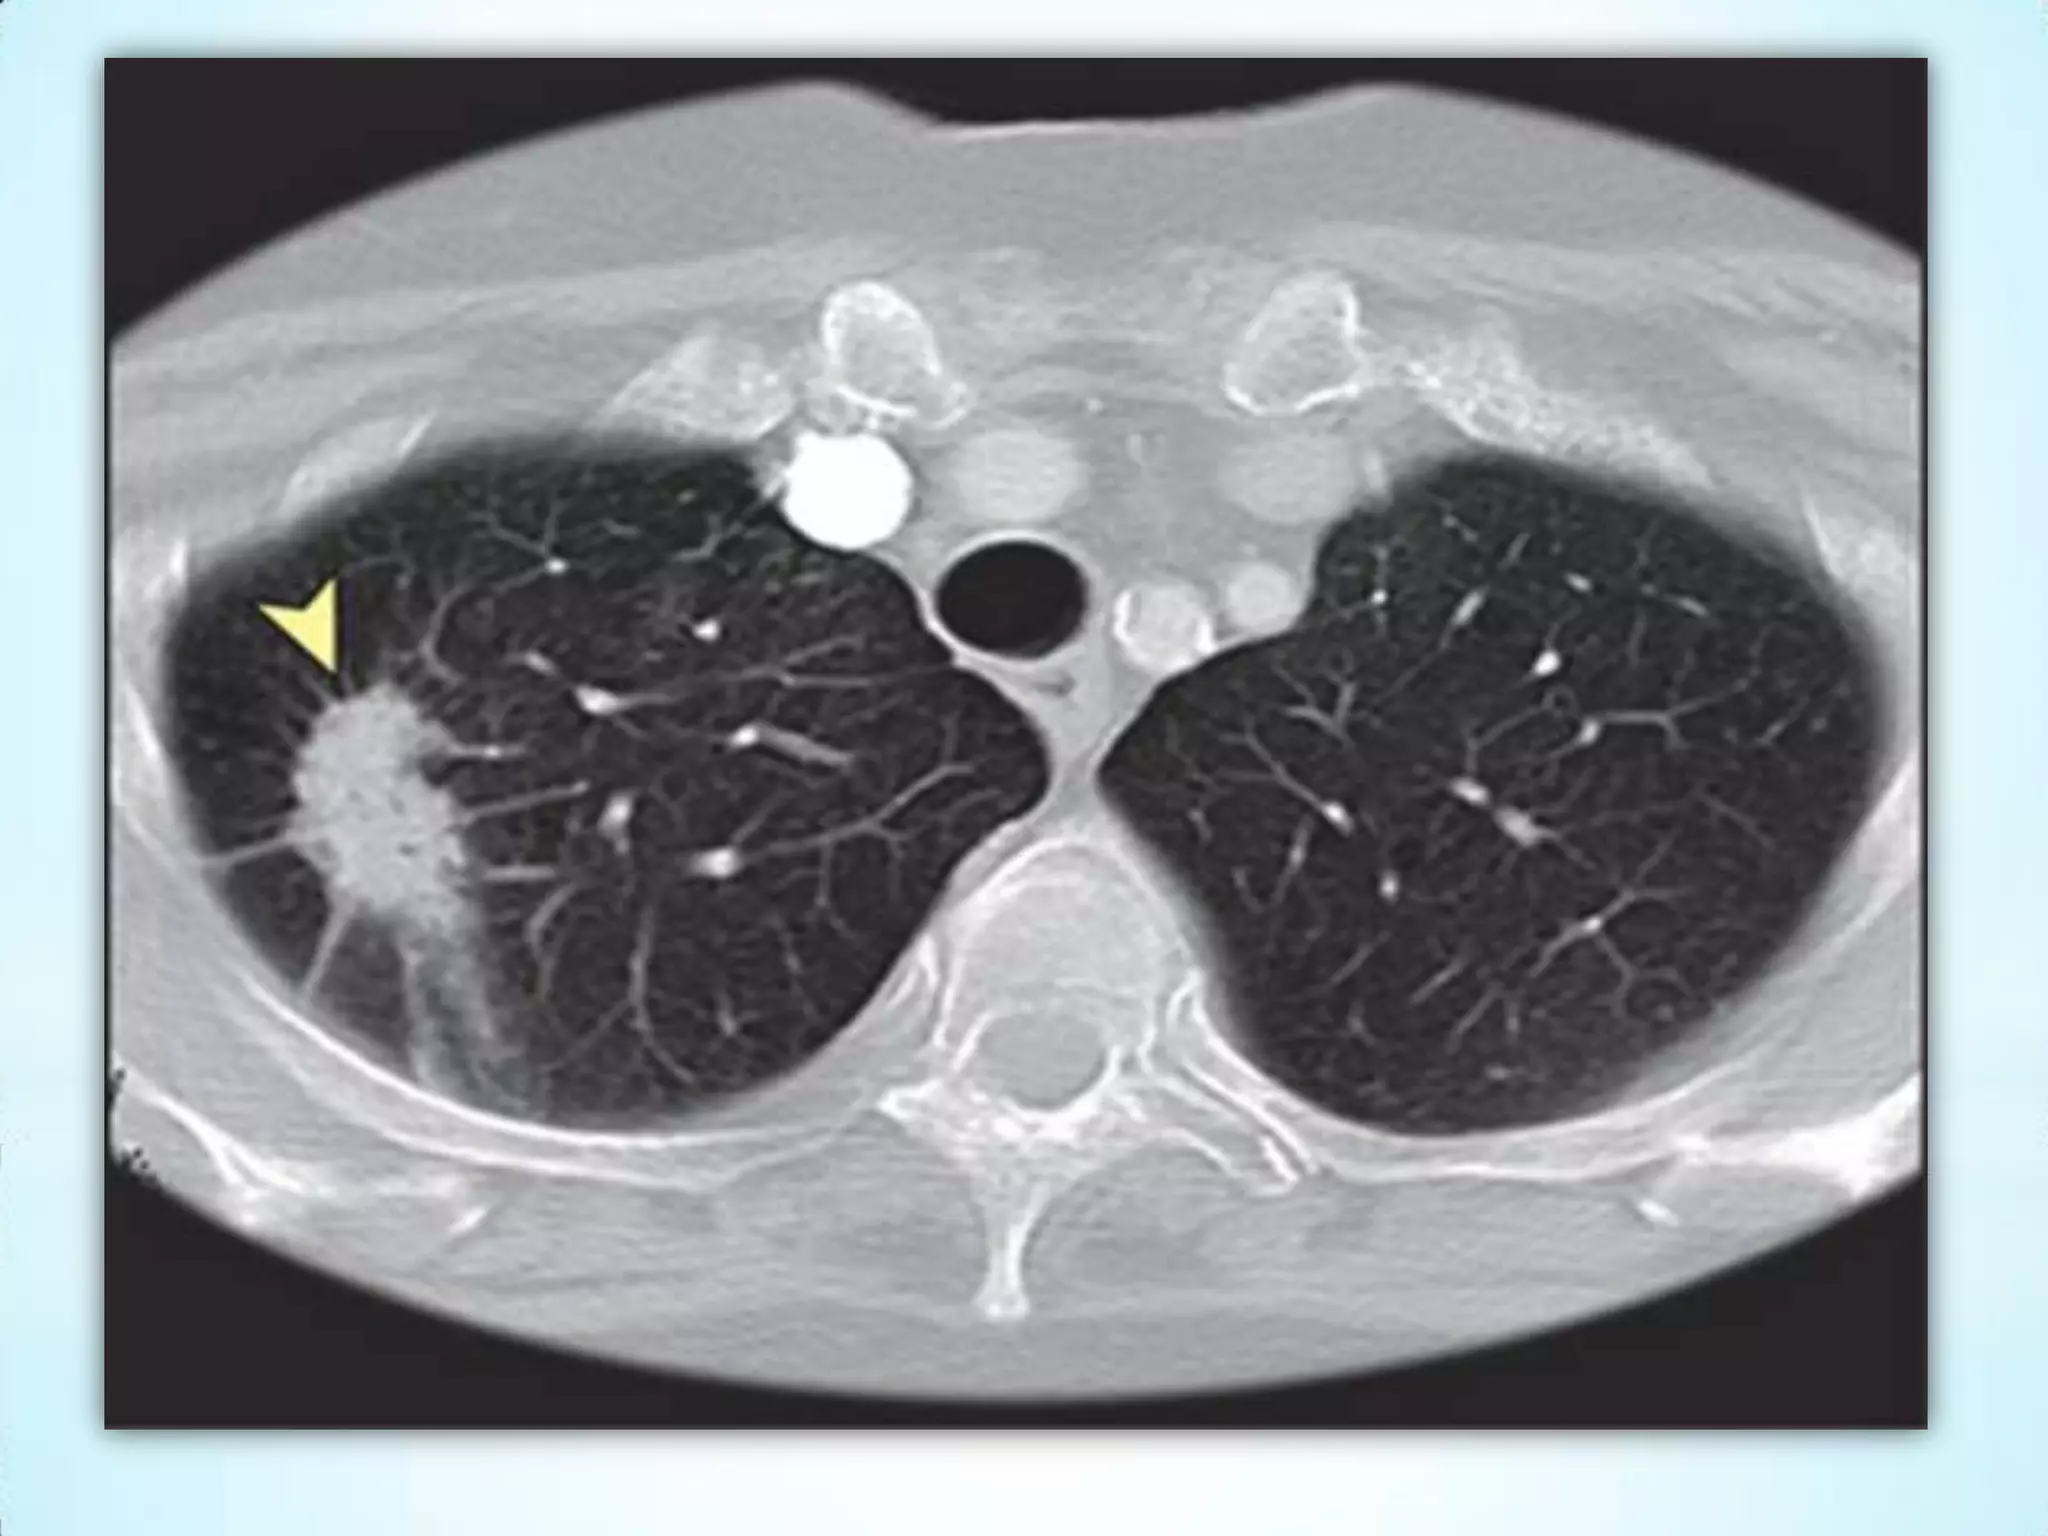

Câncer do Pulmão

O câncer de pulmão é um dos tumores malignos mais comuns, sendo

que sua incidência no mundo todo vem aumentando 2% a cada ano. A

mortalidade por esse tipo de neoplasia é muito elevada e o prognóstico

está relacionado à fase em que é diagnosticado.

O principal fator de risco para o aparecimento dessa neoplasia é o

tabagismo. Atualmente, este último corresponde a 90% dos casos desse

tumor. É mais comumente observado em homens do que em mulheres;

todavia, o número de casos em mulheres está aumentando, enquanto

que o número de casos em homens está diminuindo.

Esta neoplasia também pode ser causada por certos produtos

químicos, como:

arsênico, berílio, asbesto, radônio, níquel, cromo, cádmio e cloreto de

vinila, especialmente observados em ambiente ocupacional. Outros

fatores relacionados ao surgimento desse tumor são os

dietéticos, genéticos, histórico da DPOC e histórico de câncer de pulmão

na família.

Câncer do Pulmão Ocâncer de pulmão é um dos tumores malignos mais comuns, sendo que sua incidência no mundo todo vem aumentando 2% a cada ano. A mortalidade por esse tipo de neoplasia é muito elevada e o prognóstico está relacionado à fase em que é diagnosticado. O principal fator de risco para o aparecimento dessa neoplasia é o tabagismo. Atualmente, este último corresponde a 90% dos casos desse tumor. É mais comumente observado em homens do que em mulheres; todavia, o número de casos em mulheres está aumentando, enquanto que o número de casos em homens está diminuindo. Esta neoplasia também pode ser causada por certos produtos químicos, como: arsênico, berílio, asbesto, radônio, níquel, cromo, cádmio e cloreto de vinila, especialmente observados em ambiente ocupacional. Outros fatores relacionados ao surgimento desse tumor são os dietéticos, genéticos, histórico da DPOC e histórico de câncer de pulmão na família.